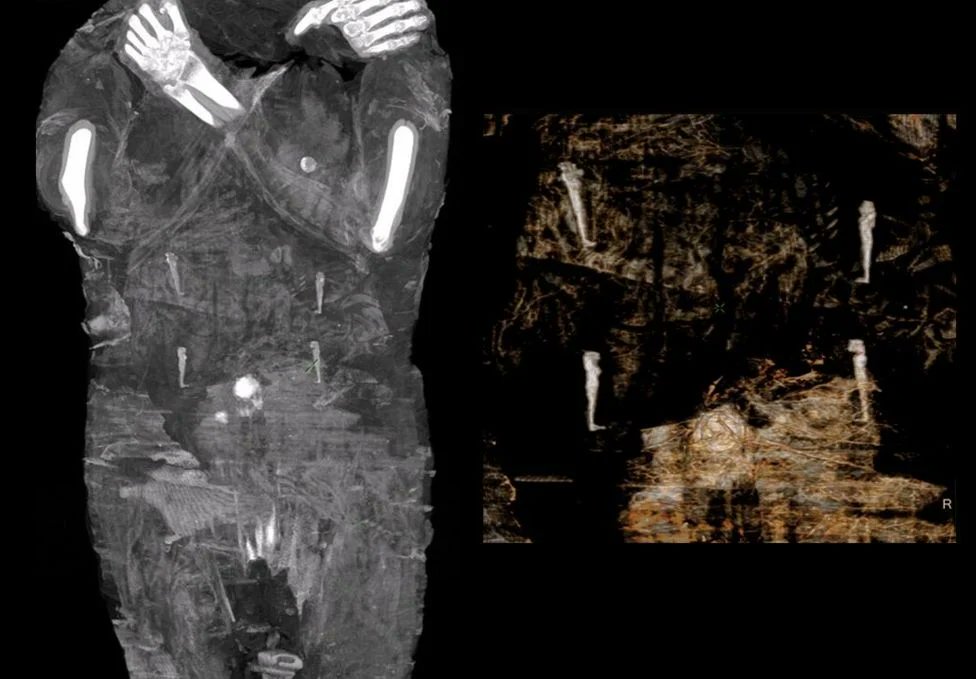

6-تم إخضاع المومياء لعدة مجموعات من التصوير المقطعي والأشعة السينية وتصور ثلاثي الأبعاد مما سمح بفحص دقيق للجنين بأكمله والذي أثبت أن المرأة كانت في الأسبوع 26-28 من الحمل

ولسوء الحظ تم الكشف عن القليل جدا عن الطفل المحنط ويقترح الخبراء أن الطفل كان ملفوفا في وضع الجنين 👇

7-على الرغم من أنهم لم يحددوا جنسه وقال" فويتشخ إيغزموند" من معهد البحر الأبيض المتوسط ​​والثقافات الشرقية في أكاديمية العلوم البولندية"لأسباب غير معروفة لم يتم إخراج الجنين من بطن المتوفية أثناء التحنيط وتم طرح العديد من النظريات لتفسير ذلك!؟ 👇